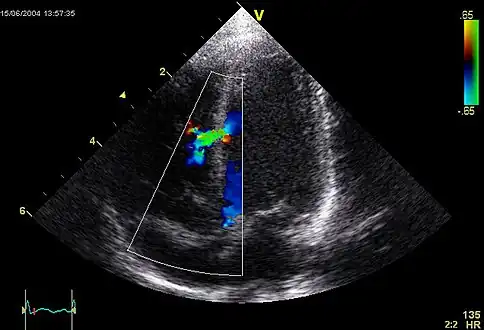

An abnormal echocardiogram: Image shows a midmuscular ventricular septal defect. The trace in the lower left shows the cardiac cycle and the red mark the time in the cardiac cycle when the image was captured. Colors are used to represent the velocity and direction of blood flow.

Echocardiography can help detect cardiomyopathies, such as hypertrophic cardiomyopathy, dilated cardiomyopathy, and many others. The use of stress echocardiography may also help determine whether any chest pain or associated symptoms are related to heart disease. The biggest advantage of echocardiography is that it is not invasive (does not involve breaking the skin or entering body cavities) and has no known risks or side effects.[6] Not only can an echocardiogram create ultrasound images of heart structures, but it can also produce accurate assessment of the blood flowing through the heart by Doppler echocardiography, using pulsed- or continuous-wave Doppler ultrasound. This allows assessment of both normal and abnormal blood flow through the heart. Color Doppler, as well as spectral Doppler, is used to visualize any abnormal communications between the left and right sides of the heart, any leaking of blood through the valves (valvular regurgitation), and estimate how well the valves open (or do not open in the case of valvular stenosis). The Doppler technique can also be used for tissue motion and velocity measurement, by tissue Doppler echocardiography.